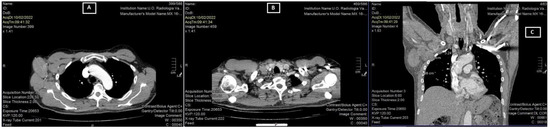

The lymphadenopathies were painful and mobile. A total body computed tomography (CT) examination confirmed the two lymphadenopathies, measuring 6.99 cm and 2.36 cm, respectively (Figure 2).

Figure 2.

CT scan revealed two lymphadenopathies: right axillary 6.99 cm (A) and supraclavicular 2.36 cm (B), and multiple adenopathies in the coronal section (C).